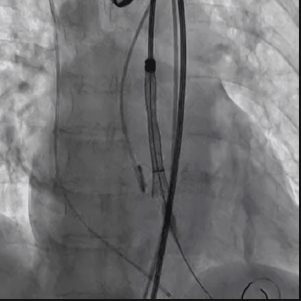

从三叶瓣重度钙化到二叶瓣畸形的根部解剖,从单纯主动脉瓣反流到入路极端迂曲挑战的案例。TaurusOne凭借其优异的柔顺性,支撑力强及内外层双侧裙边的特点,都能从容应对复杂的临床患者解剖结构。从患者的临床选择到术后的长久获益,从手术入路的种类到术中操作的注意事项,从围术期卒中的循证医学到术后的抗凝抗栓用药规范,在线专家共同交流彼此中心的围术期TAVR经验和分享现阶段经导管主动脉瓣置换的诊疗策略。针对当前TAVR领域多个热点学术问题进行了热烈的讨论,现场可谓精彩纷呈、高潮迭起。专家们纷纷借此契机相互交流探讨,分享各自的单中心经验,力求进一步提升TAVR手术的安全性和有效性,为主动脉瓣相关疾病的患者带来长远综合获益。